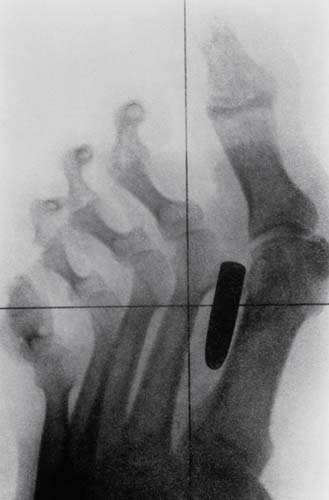

Bir erkeğin orta işaret parmağı ve orta parmak kemiklerine saplanmış bir çivi.